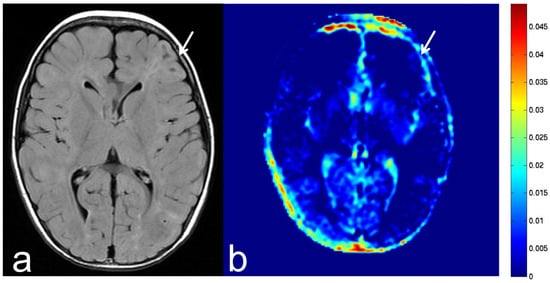

5.1. Oligodendroglioma

5.2. Diffuse Astrocytoma